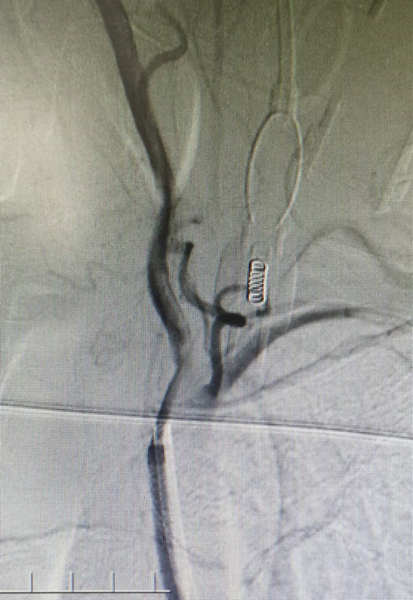

术后影像及检查

影像结论:血管成形良好,支架贴壁良好,远端显影良好。

术后支架情况:

1、病变位于颈内动脉远端,一次性低压力扩张3分钟,缓慢释放支架时间2分钟,赛诺神畅 NOVA DES®内药物洗脱支架3.0*10mm横跨狭窄,避免造成夹层。

2、赛诺神畅 NOVA DES®内药物洗脱支架降低再狭窄和支架内血栓发生的机率,顺应性较好;横向支撑力、贴壁良好。